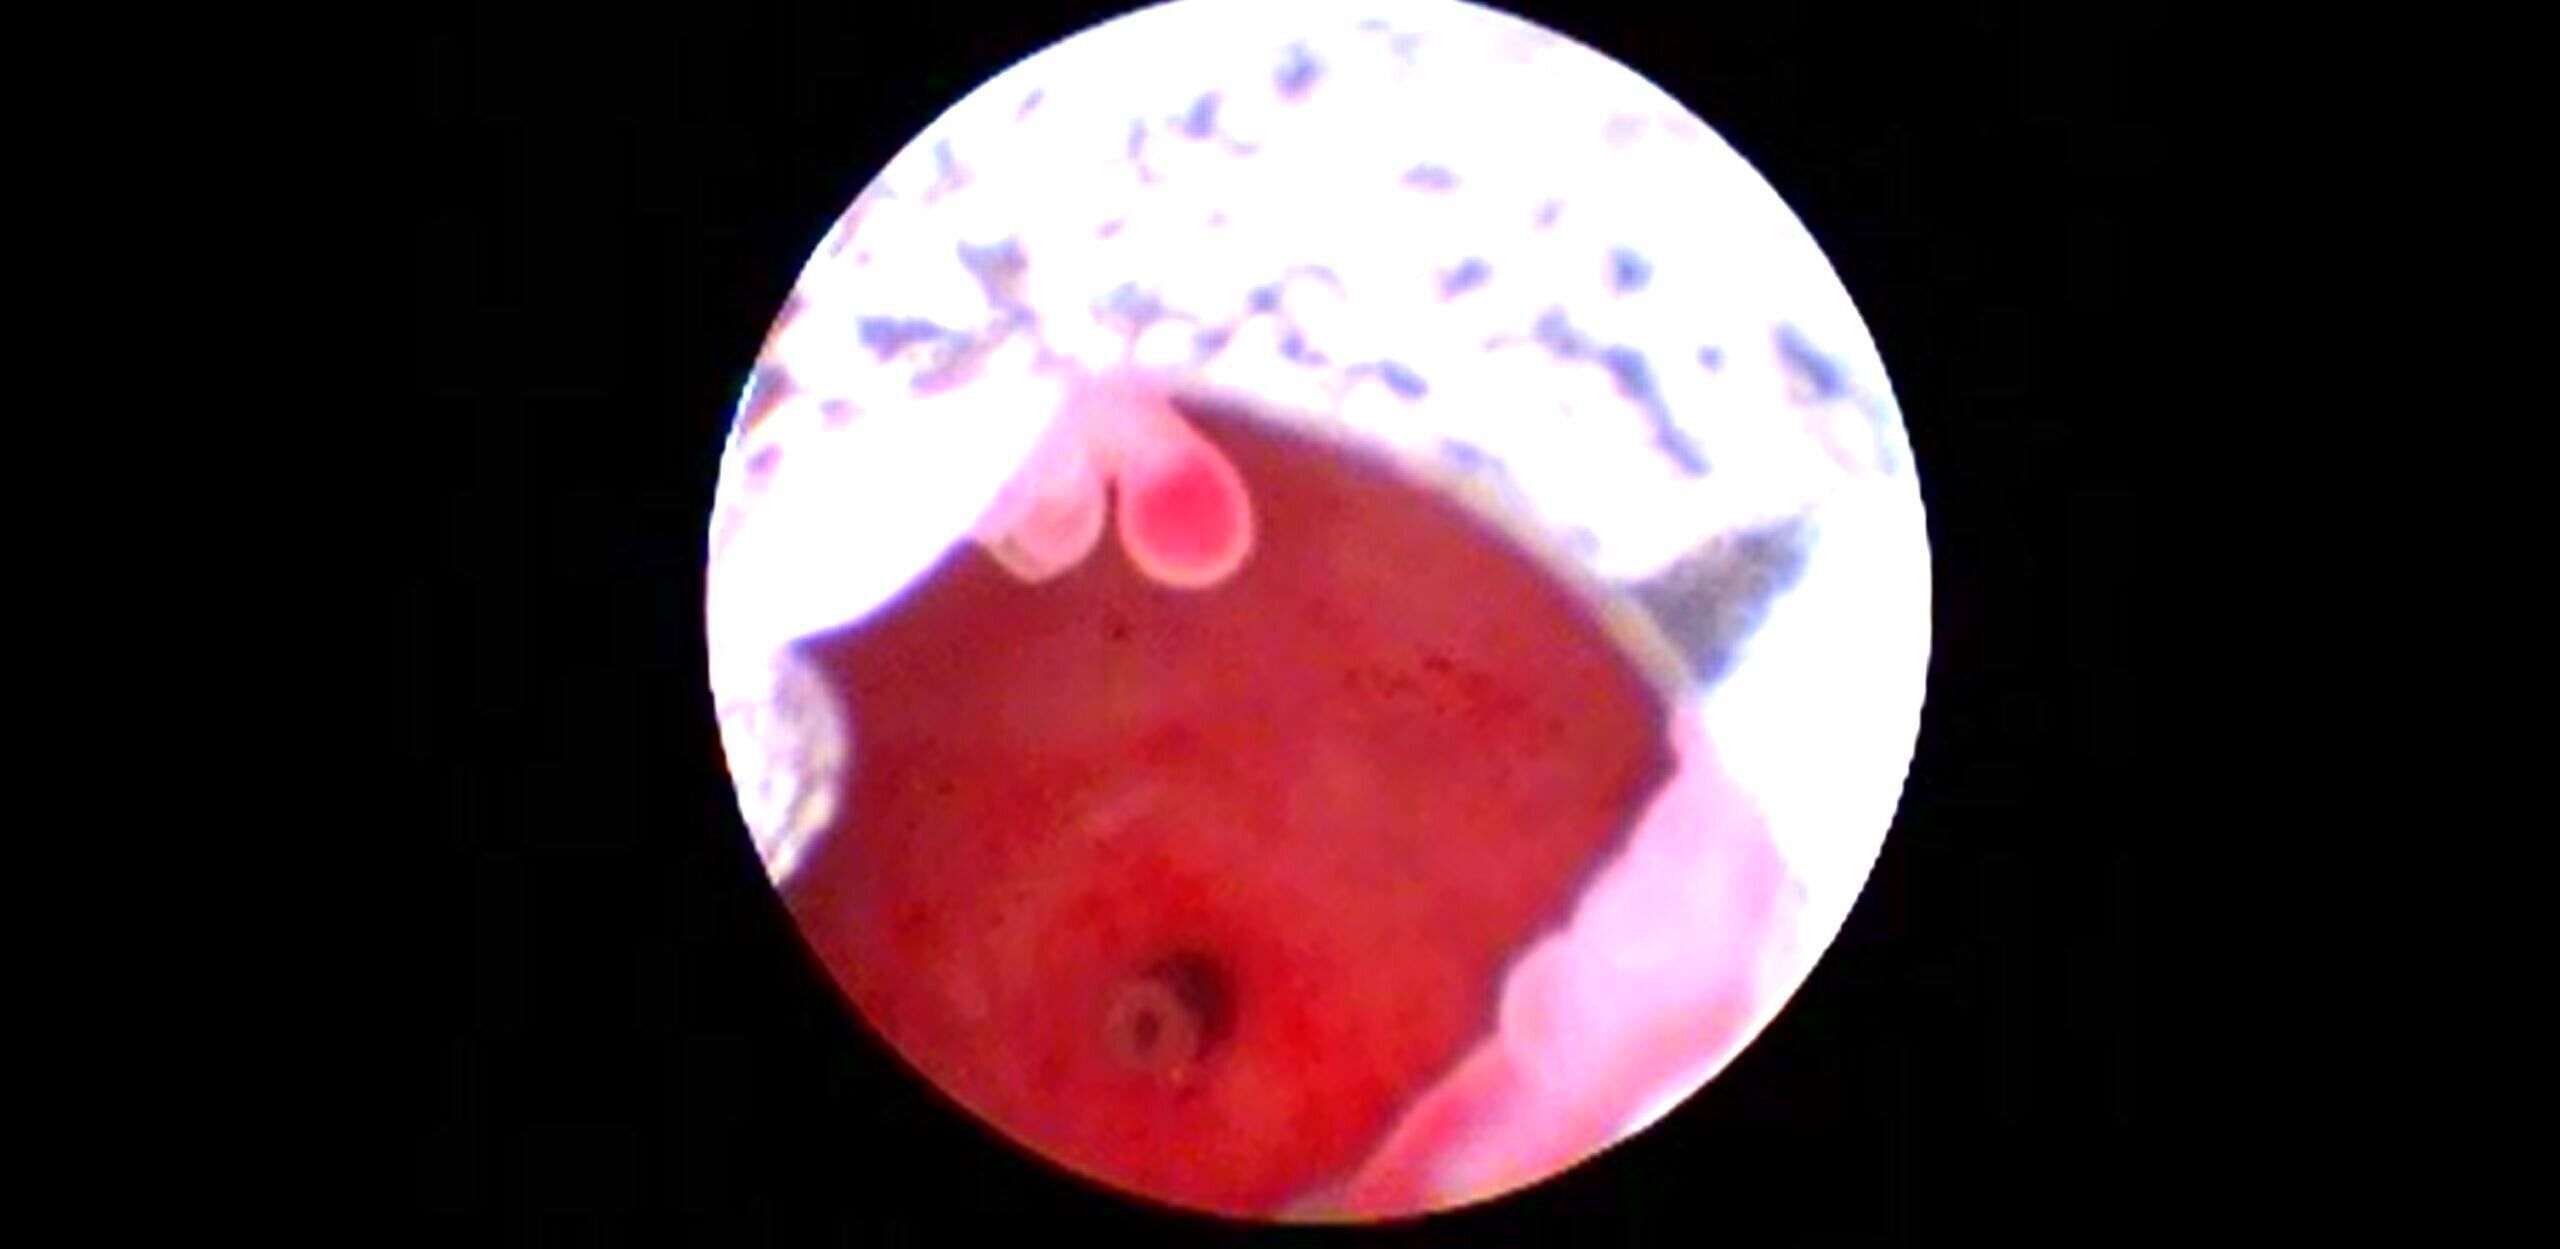

中央でさくらんぼのような形をしているのがポリープです

愛犬の頻尿が気になるときに、原因のひとつとして考えられるのが「膀胱ポリープ」です。

膀胱はオシッコをためておき、排出するための器官ですが、この内部にできもの(ポリープ)が発生すると、オシッコするときに詰まったり、粘膜が炎症を起こすことも。重症化すると命にかかわる場合もあります。とくに尿道付近のポリープは見つけにくく、「愛犬のオシッコはいつもこうだから」と見誤ると、気づくのが遅れがちになってしまいます。